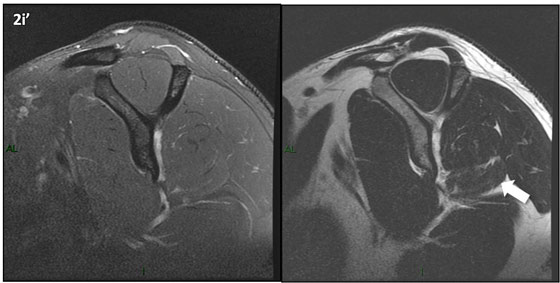

Figura 2 (a-j)': Imagens consecutivas de RM no plano sagital nas ponderaçõesT2 com supressão de gordura (DP SG) à esquerda e T2 à direita. Clique na seta para passar as imagens.

Figura 2a’ mostrando os tendões do subescapular (seta rosa), da cabeça longa do bíceps (seta verde), do supraespinhal (seta vermelha), do infraespinhal (seta laranja) e do redondo menor (seta amarela).

Figuras 2b a 2j’: Acompanhando o tendão do redondo menor (seta amarela fina) é possível notar lipossubstituição ao redor da junção miotendínea (setas amarelas grossas) e a atrofia principalmente da porção mais lateral (seta salmão). A porção mais medial (seta branca) tem volume preservado.

Repare que estas alterações também não são evidentes nas imagens com supressão de gordura no plano sagital.